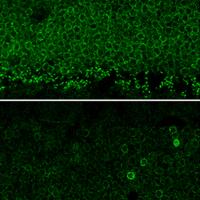

Microglia in retinal sections of a patient with retinitis pigmentosa

Immune System Can Slow Degenerative Eye Disease, NIH-led Mouse Study Shows

A new study shows that the complement system, part of the innate immune system, plays a protective role to slow retinal degeneration in a mouse model of retinitis pigmentosa, an inherited eye disease.

Immune cells in the retina can spontaneously regenerate

Immune cells called microglia can completely repopulate themselves in the retina after being nearly eliminated, according to a new study in mice from scientists at the National Eye Institute (NEI).